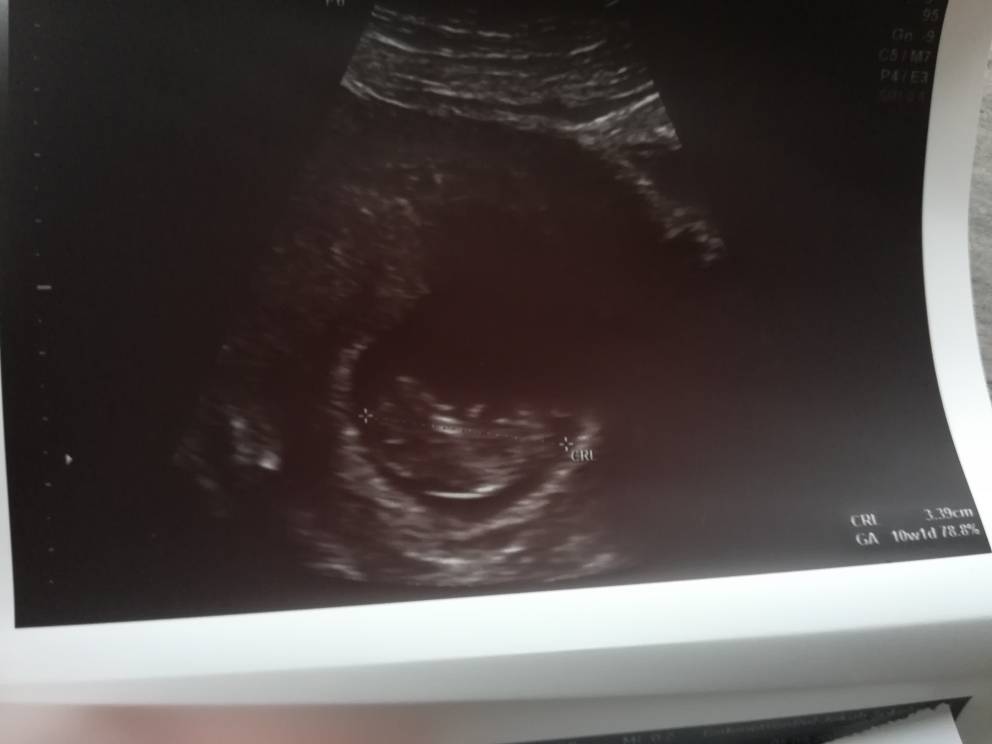

Wczoraj byłam na wizycie. Według OM był to 7 tydzien 6 dni, a na USG pokazało 8 tydzień 2 dni. ( na poprzednim USG pokazywało, ze ciąża jest tydzień młodsza, także dzidziuś rośnie jak na drożdzach

) Dzidziuś ma ponad 1,5 cm. Serduszko bije, słyszałam i mam nagrane